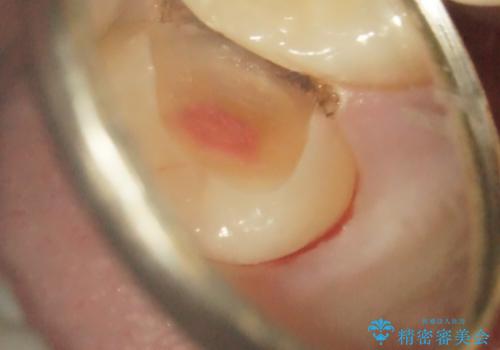

- 奥歯がズキズキ痛いことを主訴に来院されました。

根管治療を行なったのち、オールセラミッククラウンにて修復治療を行なっております。

根管治療を行なった歯は速やかに歯冠修復が必要です。